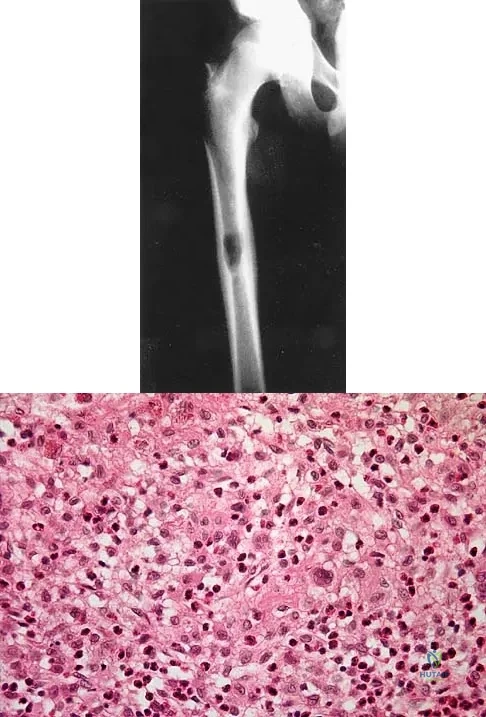

A previously healthy 13-year-old girl has had thigh pain for the past 3 weeks. The radiograph shown in Figure 47a reveals a lesion in the right femur. A bone scan and CT scan of the chest show no evidence of other lesions. A biopsy specimen is shown in Figure 47b. What is the most likely diagnosis?

Explanation